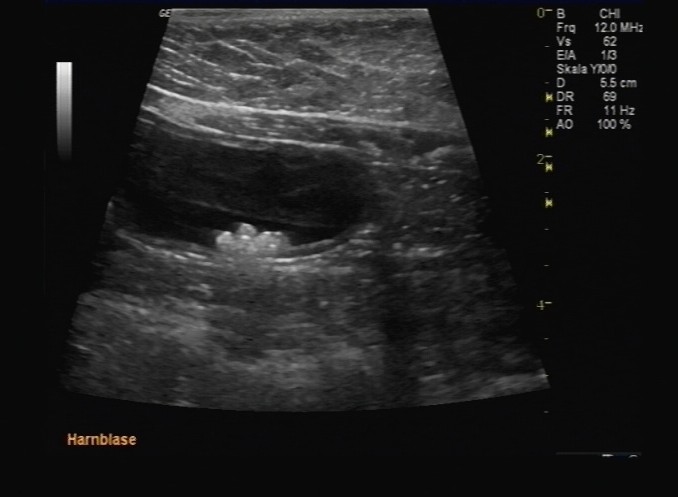

Sonografie

Für viele Fragestellungen der inneren Medizin benötigt man eine Ultraschalluntersuchung. Ob Trächtigkeitsuntersuchung, Tumorsuche, Herzbeutelerguss-Punktion, Schilddrüsenbeurteilung, Augenuntersuchung beim grünen Star ... die Sonografie liefert uns in nahezu jede Körperregion einen Einblick. Ausgenommen sind Lunge, Mediastinum und Beckenhöhle da Luft und Knochen die Schallausbreitung behindern. Die Qualität der Untersuchung hängt vor allem von den verfügbaren Sonden ab. Unser Phillips Affinity-Ultraschallgerät ist für den Bauchultraschall mit zwei Schallköpfen unterschiedlicher Eindringtiefe ausgestattet und ermöglicht uns die Untersuchung kleinster Tiere und feinster Strukturen aber auch die von sehr großen und schweren Patienten. Mehr als 20 Programme zur Feinjustierung sorgen für den „optimalen Durchblick“ bei jedem Patienten. Wir führen unsere sonografischen Untersuchungen stets ruhig und stressarm durch und benötigen nur in Ausnahmefällen eine Sedierung. Nur ein wenig Geduld müssen unsere Patienten mitbringen, denn ein guter Ultraschall braucht Zeit.

Bitte beachten sie, dass ihr Tier für die Untersuchung möglichst nüchtern sein sollte!!